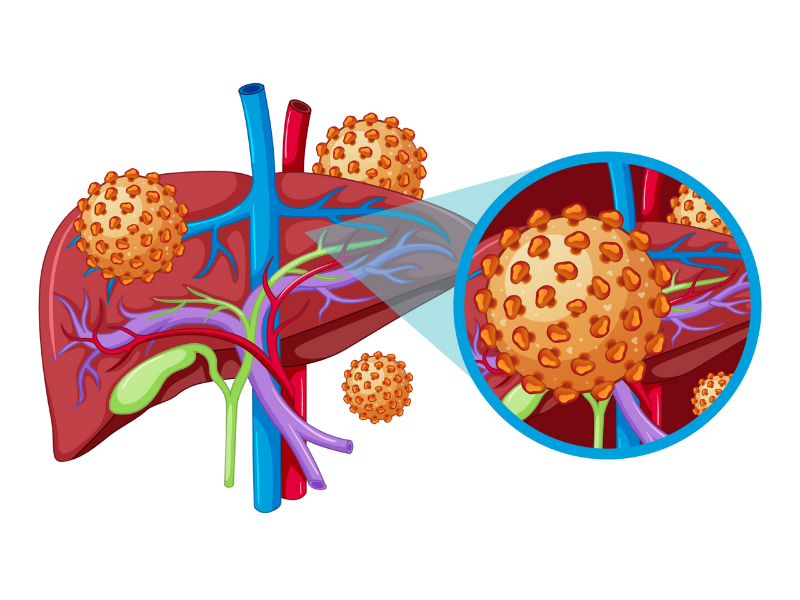

Liver transplant is a complex but life-saving procedure for patients with severe liver disease, liver failure, or certain liver cancers. It involves replacing a diseased liver with a healthy one from a living or deceased donor. At our Liver Transplant and HPB Surgery Care center, we provide comprehensive care for both adults and children, ensuring safety, precision, and excellent outcomes.